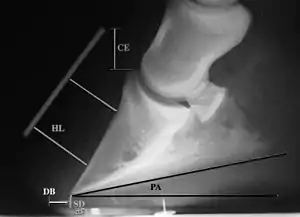

Radiographs are an important part of evaluating the laminitic horse. They not only allow the practitioner to determine the severity of the episode, which does not always correlate with degree of pain,[1] but also to gauge improvement and response to treatment. Several measurements are made to predict severity. Additionally, radiographs also allow the visualization and evaluation of the hoof capsule, and can help detect the presence of a lamellar wedge or seromas.[1] The lateral view provides the majority of the information regarding degree of rotation, sole depth, dorsal hoof wall thickness, and vertical deviation.[1][17] A 65-degree dorsopalmar view is useful in the case of chronic laminitis to evaluate the rim of the coffin bone for pathology.[1]

Several radiographic measurements, made on the lateral view, allow for objective evaluation of the episode.

- Coronary extensor distance (CE): the vertical distance from the level of the proximal coronary band to the extensor process of P3. It is often used to compare progression of the disease over time, rather than as a stand-alone value. A rapidly increasing CE value can indicate distal displacement (sinking) of the coffin bone, while a more gradual increase in CE can occur with foot collapse. Normal values range from 0–30 mm, with most horses >12–15 mm.[1]

- Sole depth (SD): the distance from the tip of P3 to the ground.

- Digital breakover (DB): distance from the tip of P3 to the breakover of the hoof (dorsal toe).[1]

- Palmar angle (PA): the angle between a line perpendicular to the ground, and a line at the angle of the palmar surface of P3.

- Horn:lamellar distance (HL): the measurement from the most superficial aspect of the dorsal hoof wall to the face of P3. 2 distances are compared: a proximal measurement made just distal to the extensor process of P3, and a distal measurement made toward the tip of P3. These two values should be similar. In cases of rotation, the distal measurement will be higher than the proximal. In cases of distal displacement, both values will increase, but may remain equal. Therefore, it is ideal to have baseline radiographs for horses, especially for those at high-risk for laminitis, to compare to should laminitis ever be suspected. Normal HL values vary by breed and age:[1]